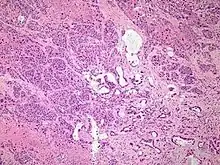

Histopathology

The most common form of pancreatic cancer (adenocarcinoma) is typically characterized by moderately to poorly differentiated glandular structures on microscopic examination. There is typically considerable desmoplasia or formation of a dense fibrous stroma or structural tissue consisting of a range of cell types (including myofibroblasts, macrophages, lymphocytes and mast cells) and deposited material (such as type I collagen and hyaluronic acid). This creates a tumor microenvironment that is short of blood vessels (hypovascular) and so of oxygen (tumor hypoxia).[2] It is thought that this prevents many chemotherapy drugs from reaching the tumor, as one factor making the cancer especially hard to treat.[2][3]

Cancer type | Relative incidence[11] | Microscopy findings[11] | Micrograph | Immunohistochemistry markers[11] | Genetic alterations[11] |

---|---|---|---|---|---|

Pancreatic ductal adenocarcinoma (PDAC) | 90% | Glands and desmoplasia | ![]() | ||

Pancreatic acinar cell carcinoma (ACC) | 1% to 2% | Granular appearance | ![]() |

||

Adenosquamous carcinoma | 1% to 4%[58] | Combination of gland-like cells and squamous epithelial cells. | ![]() | Positive for:

Negative for: |

|

Pancreatic neuroendocrine tumor | 5% | Multiple nests of tumor cells | ![]() | ||